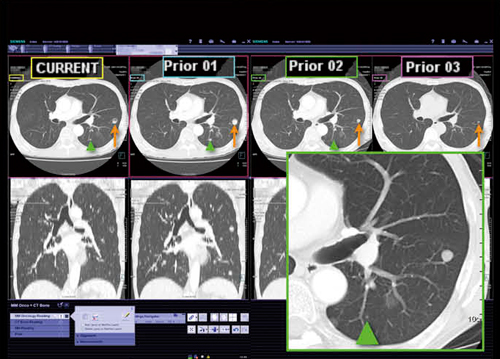

MM Readingは,異なるモダリティや過去画像をPACSビューワのように一覧して,比較,読影が可能である。図2は,今回と過去画像を並べて表示したsyngo.viaの画面だが,一見してPACSビューワのようにしか見えず,違和感なく読影可能である。タブでオーバービューや比較(Compare)などを切り替えられる。

図2 MM Reading

今回と過去シリーズとを並べて表示

syngo.viaの位置合わせ機能では,同じ患者の検査日の異なる複数のシリーズを読み込むと,何も操作することなく各画像のスライス位置が同期された状態で表示される(図3)。各画像のスライス位置の数値はバラバラであり,位置ではなく,形状からスライスを一致させていることがわかる。

肺野領域の5mm厚で撮影された画像でも,異なる4回分の画像で肺転移病変(↑)のあるスライスが表示されている(図4)。この画像ではもう1つ非常に小さな病変(▲)があるが,この病変についてもスライスが同期されており,syngo.viaが精度の高い位置合わせ機能を有していることがわかる。

図3 MM Oncology

位置合わせ機能で異なるシリーズを同期させて表示

図4 MM Oncology

肺野5mm厚画像での4回分の検査の比較